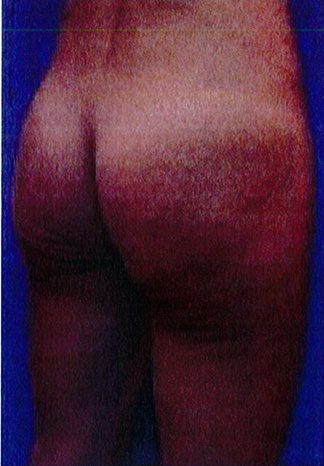

Hình. 20. (A) Hình anh trước và (B) và sau phẫu thuật làm đầy mông của bệnh nhân có vùng mông tương đối đầy đặn. Bệnh nhân được đặt khối implant dưới cân thể tích 330 mL ở hai bên.

THỜI GIAN HỒI PHỤC SAU MỔ

Bệnh nhân 30 tuổi mong muốn cải thiện hình dáng vòng ba, mặc dù vòng mông đã tương đối đây đặn. Bác sĩ sau khi đánh giá đã đưa ra quyết định hút mỡ eo và làm đầy mông bằng implant. Hai khối implant microtextured (vi nhám) thể tích 330 mL được đặt cân đối ở hai bên. Bệnh nhân sau phẫu thuật xuất hiện bục một phần vết mổ (dài khoảng 2cm) ở hai bên nhưng không sâu và đã điều trị kịp thời bằng dung dịch sát khuẩn, kháng sinh tại chỗ và toàn thân. Vết mổ liền lại tốt (Hình 20).